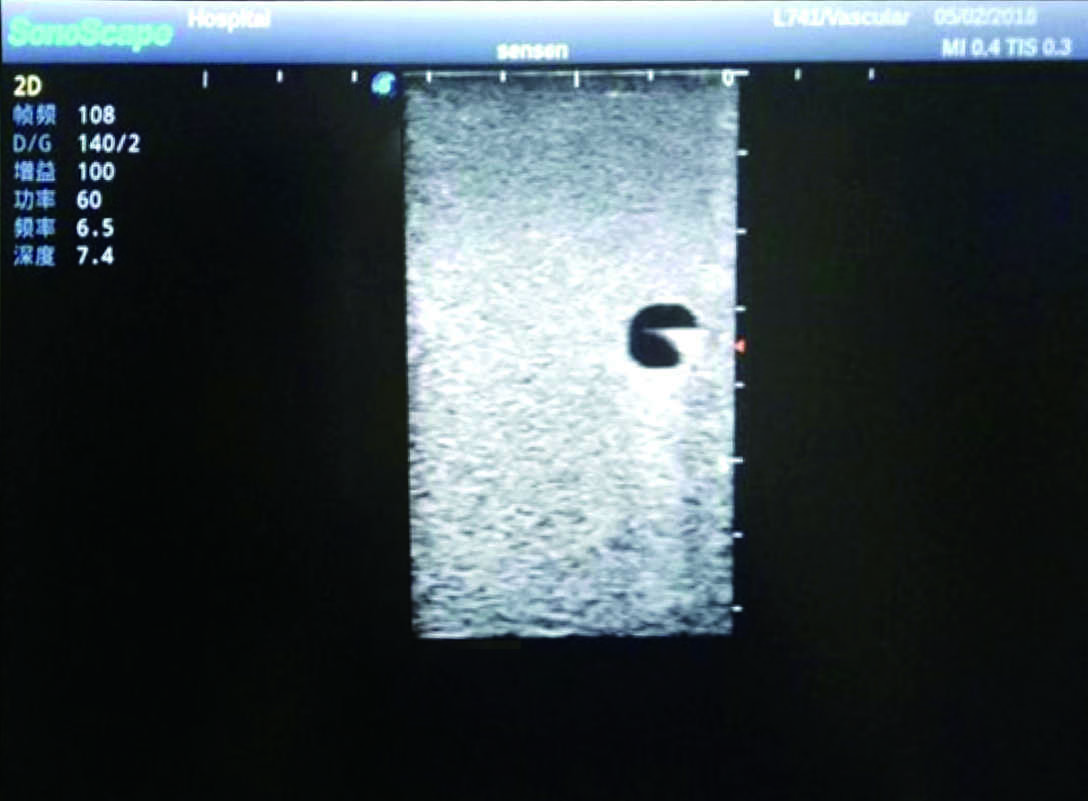

5)   Observe the guide wire marches

6)   Detect whether the catheter is properly placed